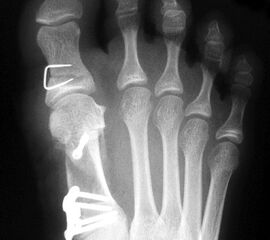

Beim Follow up nach 6 Monaten zeigte sich eine Korrektur des ersten Intermetatarsalwinkels (IMW) um durchschnittlich 9° (Range 4-15°) auf Normwerte (6,8° SD 1,3) (Abb. 21).

Gutes postoperatives Ergebnis mit physiologischem Intermetatarsale I-II Winkel nach open wedge Osteotomie.

Abbildung 21

In zwei Fällen kam es intraoperativ zu einem Bruch der lateralen Kortikalis. In einem Fall konnte durch die winkelstabile Platte eine ausreichende Stabilität erzielt werden, in dem anderen Fall wurde zusätzlich ein perkutaner Kirschnerdraht eingebracht, der nach 6 Wochen entfernt wurde. Eine stabile knöcherne Konsolidierung der Osteotomie ohne Korrekturverlust konnte in beiden Fällen erreicht werden. Die Analyse der Röntgenaufnahmen ergab eine Verlängerung des Os metatarsale I von durchschnittlich 1,8 mm (Range 1-4 mm).